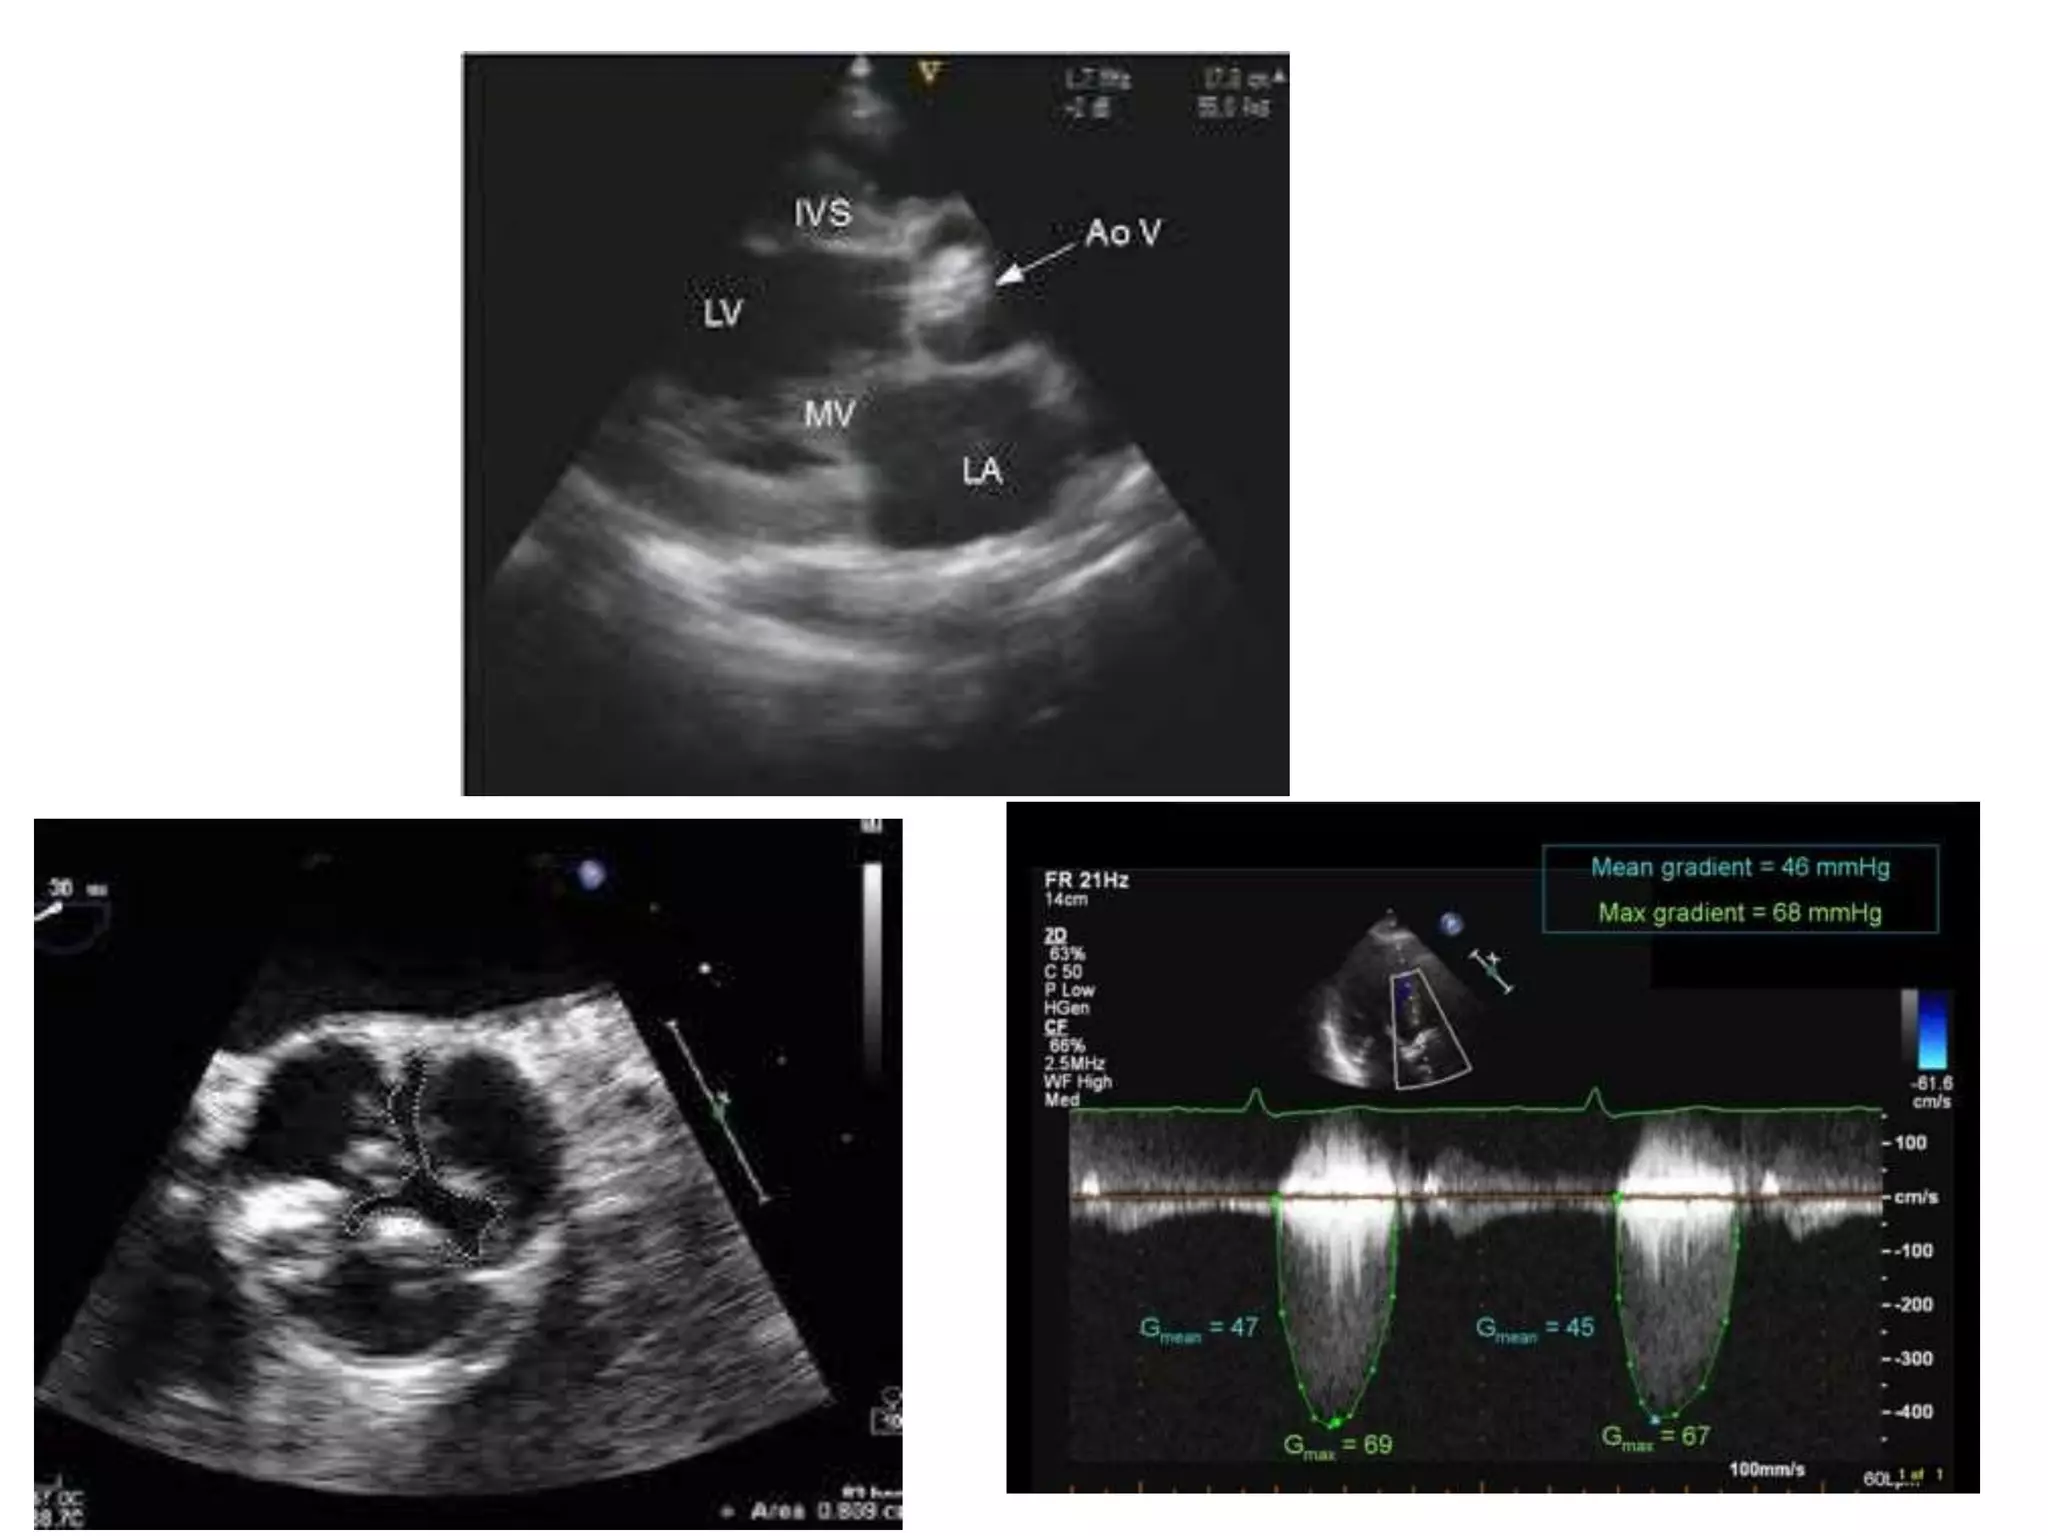

AS

MS Changes in MVarea with severity of MS Normal valve : 4–6 cm2 Mild MS : 2–4 cm2 Moderate MS : 1–2 cm2 Severe MS : <1 cm2. Criteria for diagnosis of severe MS (many derived from Doppler) • Measured valve orifice area <1 cm2 • Mean pressure gradient >10 mmHg • Pressure half-time >200 ms • Pulmonary artery systolic pressure >35 mmHg.